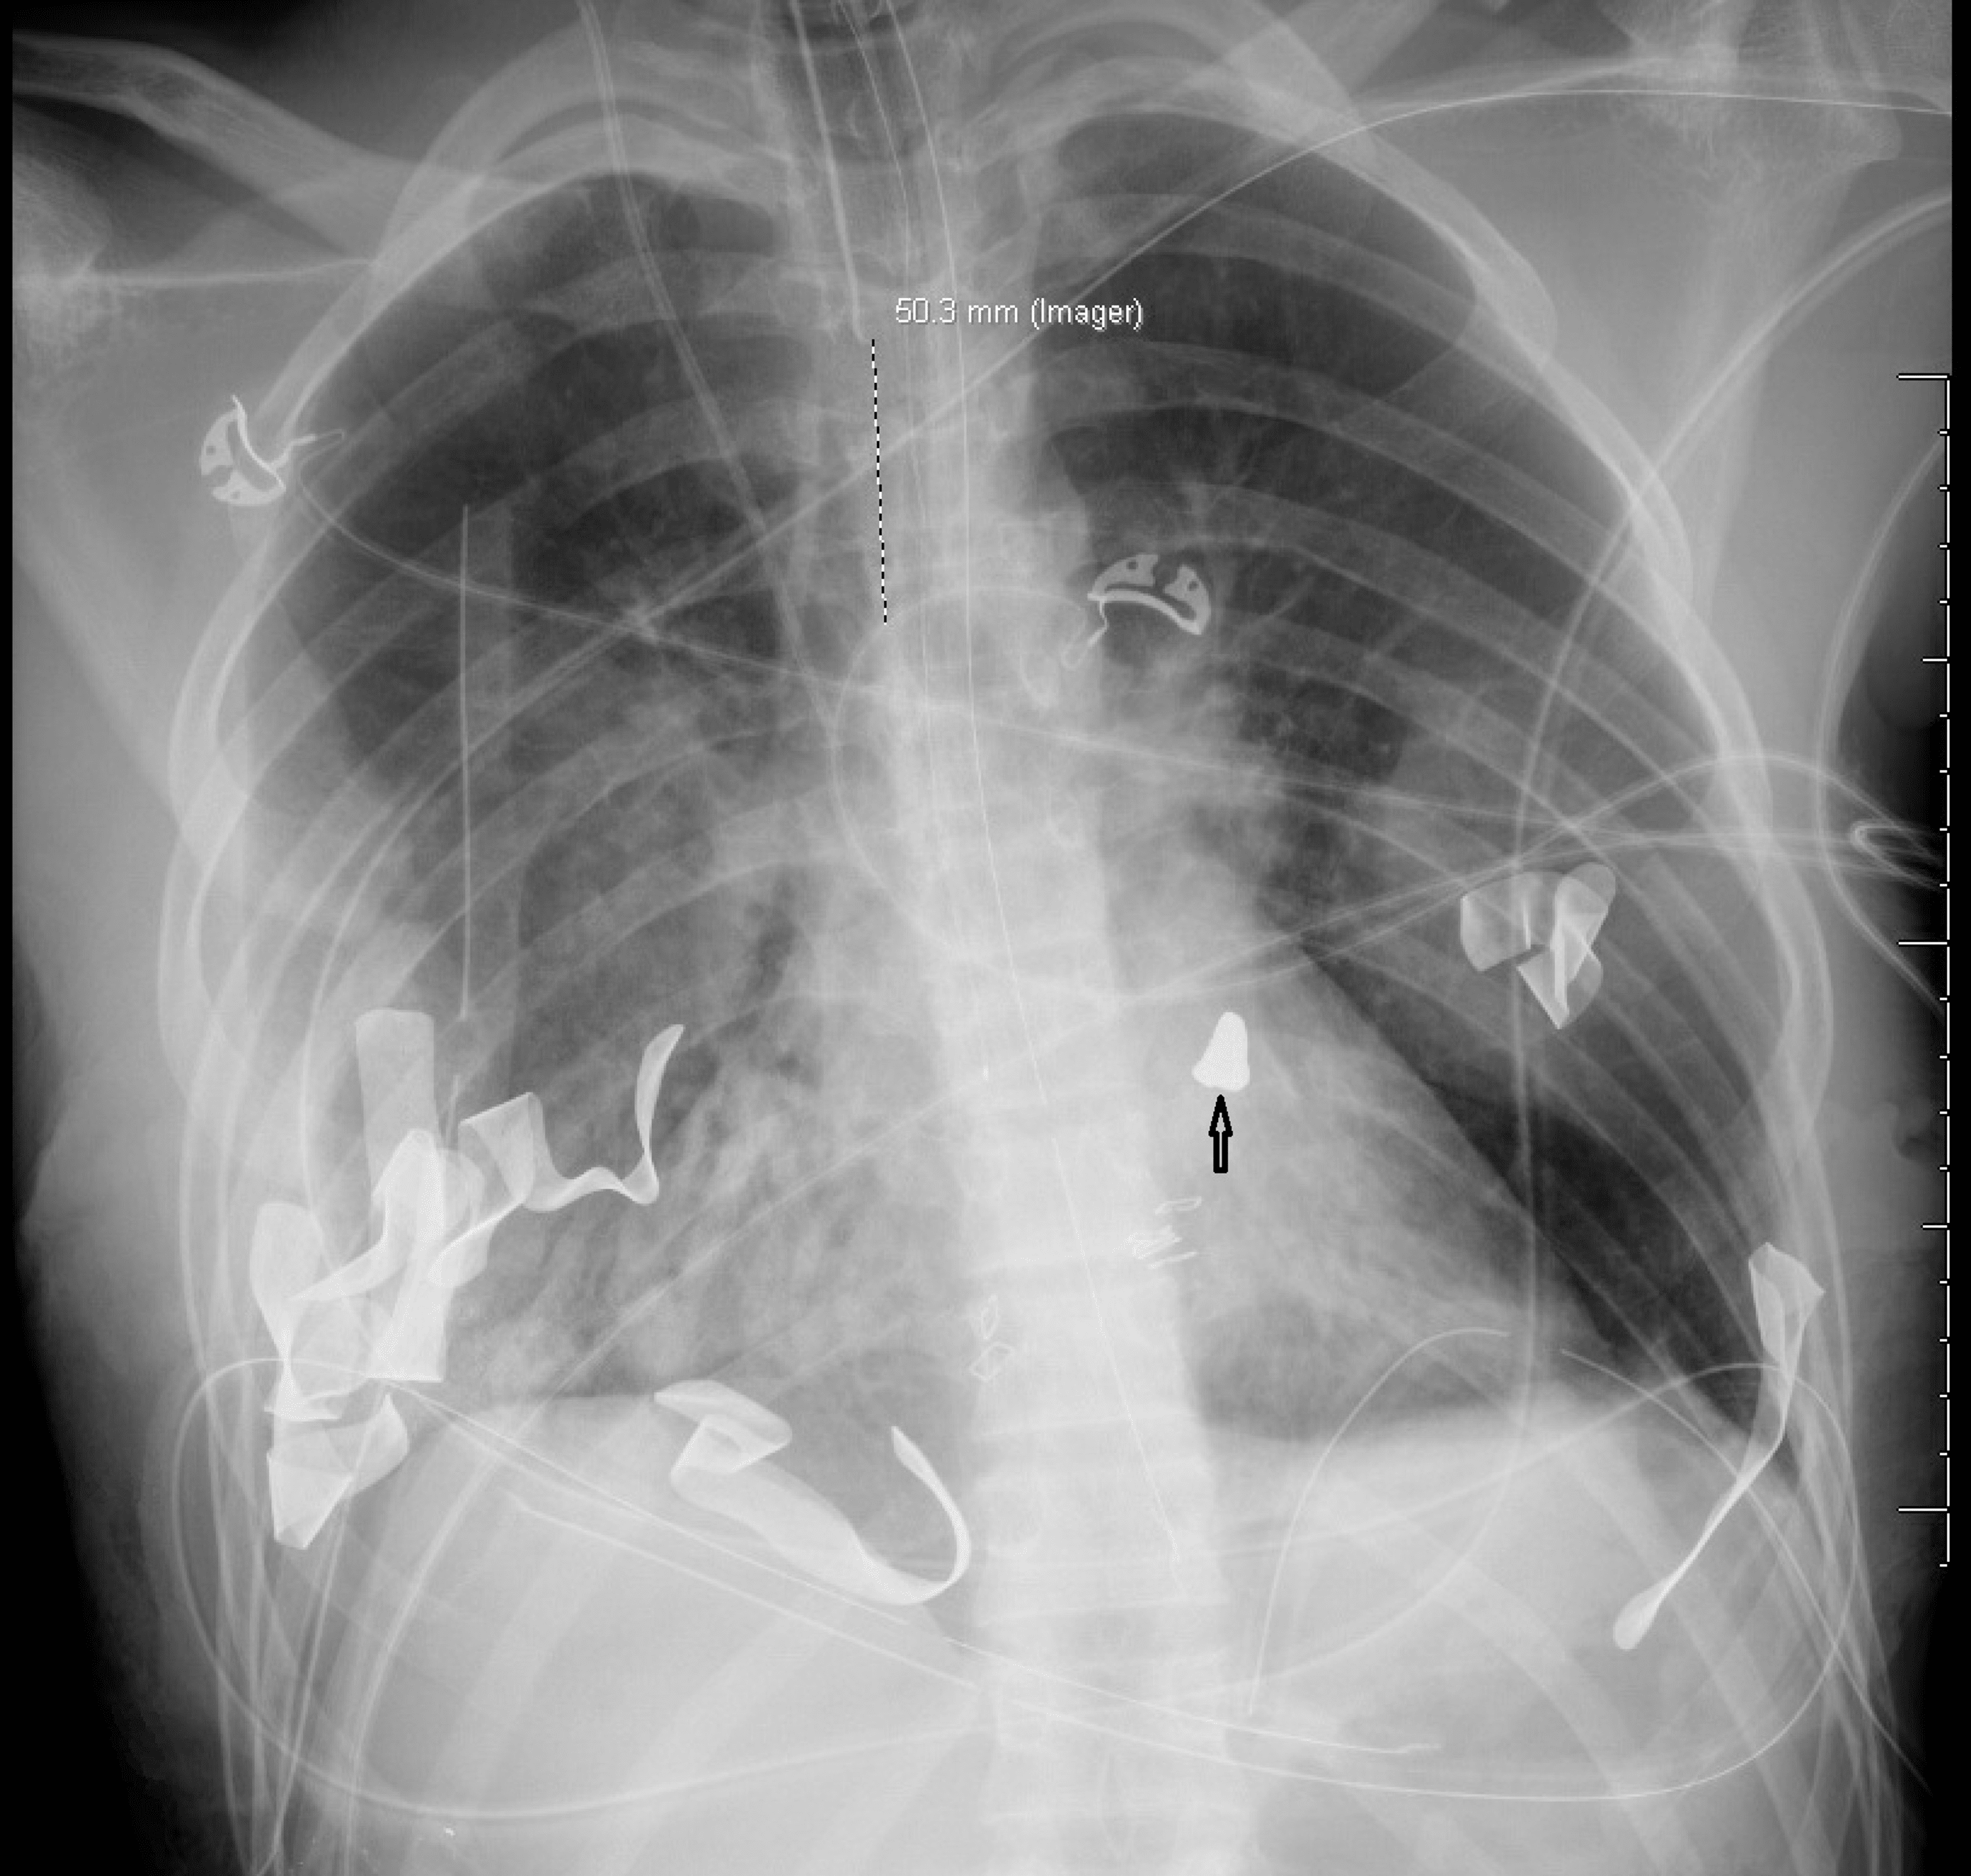

Cureus | Gunshot Wound to the Chest With Retained Epicardial Bullet

Intra-Aortic Missile After Gunshot Wound to Chest: An Interesting Case …

Thoracic gunshot wound | Radiology Case | Radiopaedia.org